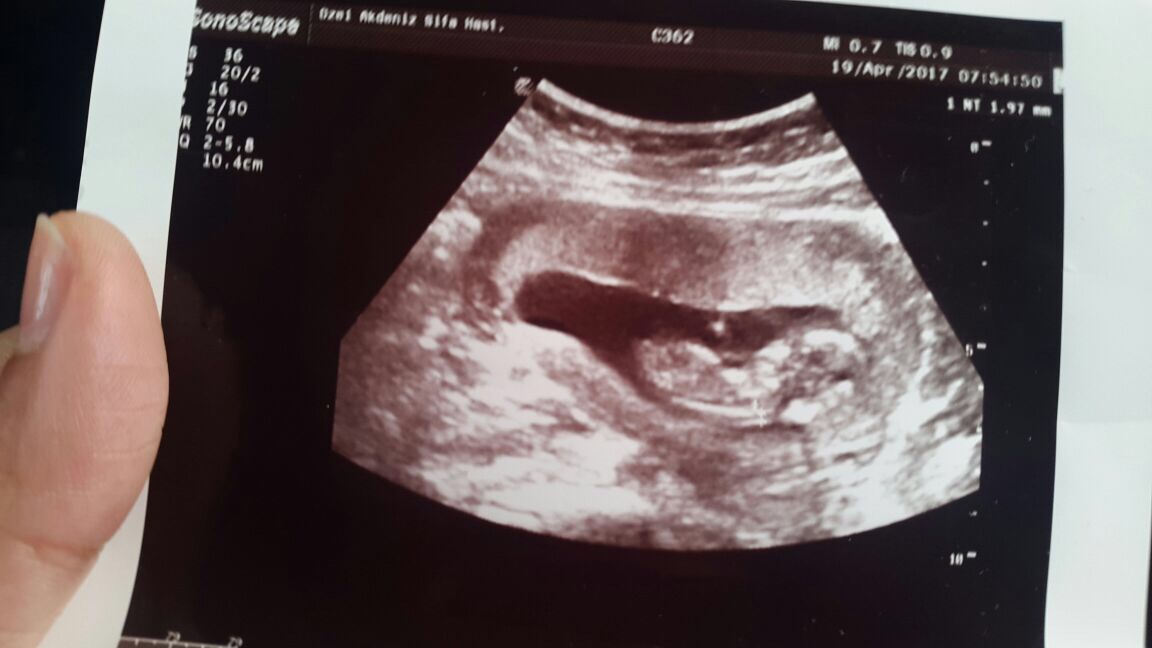

Bagdat1987 Yeni Üye Üye 21 Nisan 2017 #238 Benimki de bu 🙂 inşallah kısa süre de görürsünüz mesajımı 12+3 haftalık Ekli dosyalar IMG_0120.JPG 94,2 KB · Görüntüleme: 879

Bagdat1987 Yeni Üye Üye 21 Nisan 2017 #239 Benimki de bu 🙂 inşallah kısa süre de görürsünüz mesajımı 12+3 haftalık Ekli dosyayı görüntüle 76118